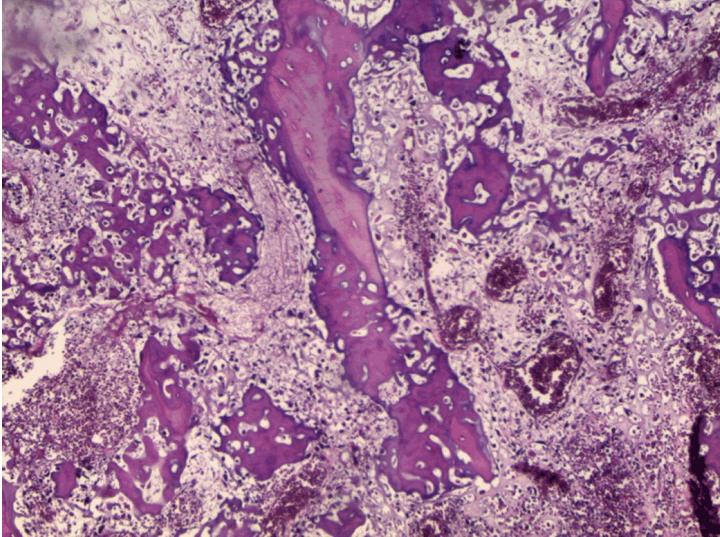

At the pathology laboratory, we received a piece of the left lower limb amputation. (Figure 2) We opened it. Gross examination of the resected distal femur revealed a 22x5 cm intramedullary multicystic hemorrhagic destructive tumor with cortical destruction and extension into the adjacent anterior and posterior soft tissues. The latter component of the mass was larger than the intraosseous tumor. (Figure 3) The articular surface was not involved. We cut the femur in its longest axis with electric saw. (Figure 4) Fixation in 10% neutral buffered formalin for 48 hours and decalcification of bone with nitric acid were performed. Slice of bone section was included in full. Many specimens from soft tissues and the surgical margins were also taken. Microscopic view of histological specimens of tumor stained with hematoxylin andeosin showed prominent blood filled cysts with malignant stroma in septa separating cysts. (Figure 5) (Figure 6) It contained atypical tumor cells oval or round of variable size with osteoblast-like multinucleated giant cells and a variable amount of immature osteoid. (Figure 7) (Figure 8) (Figure 9) (Figure 10) (Figure 11) (Figure 12) Numerous mitotic figures were noted (Figure 13). The tumor was located at 6 cm from the bone limit and 2 cm at the edge of the soft tissues. The resection margins were negative. The marrow, scooped and submitted separately, was negative.

Figure 5: Low magnification showing large blood-filled cystic spaces with septa composed of loose hemorrhagic tissue with sarcomatous cells (H&E stain, x400).

Figure 6: Medium-power magnification shows cystic spaces without lining surrounded by septa containing highly atypical malignant cells (H&E stain, x100).